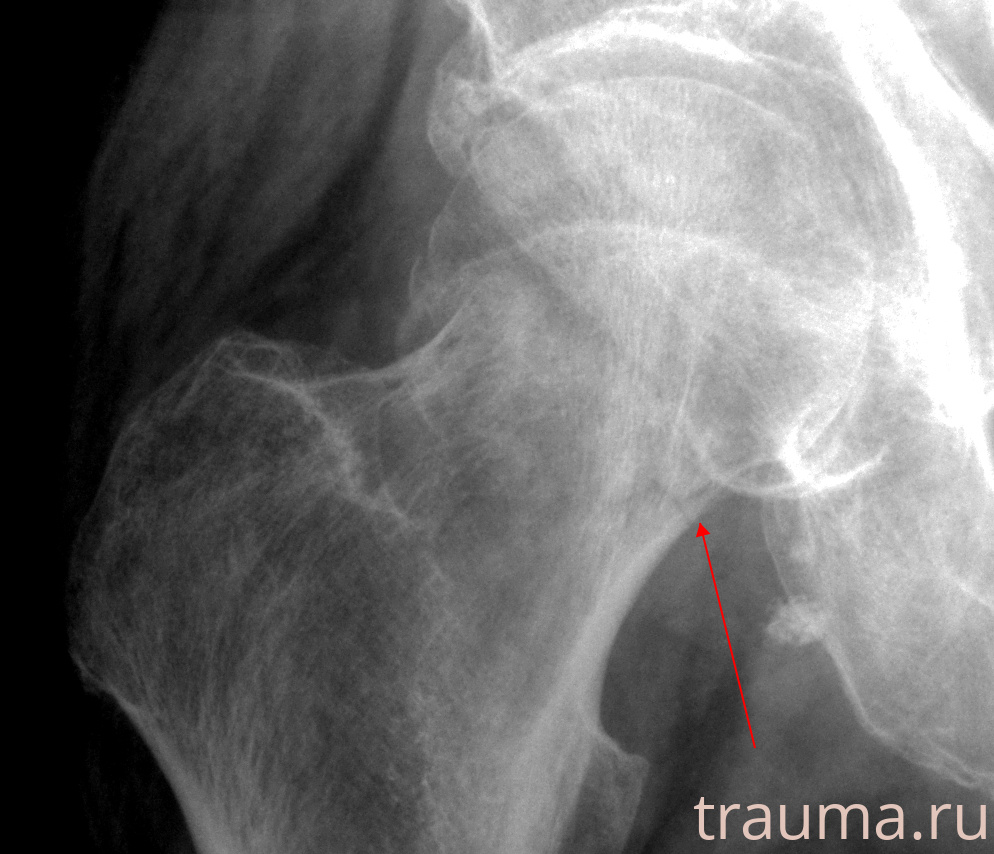

Рентгенограммы

Рентген на дому: по вашему адресу приезжает врач-рентгенолог, травматолог-ортопед с мобильным рентгеновским аппаратом, проводит диагностику травмы или заболевания, делает необходимые рентгенограммы, дает рекомендации по дальнейшему лечению. Получить качественные снимки в домашних условиях возможно благодаря уникальной методике, разработанной МосРентген Центром для института  Склифосовского